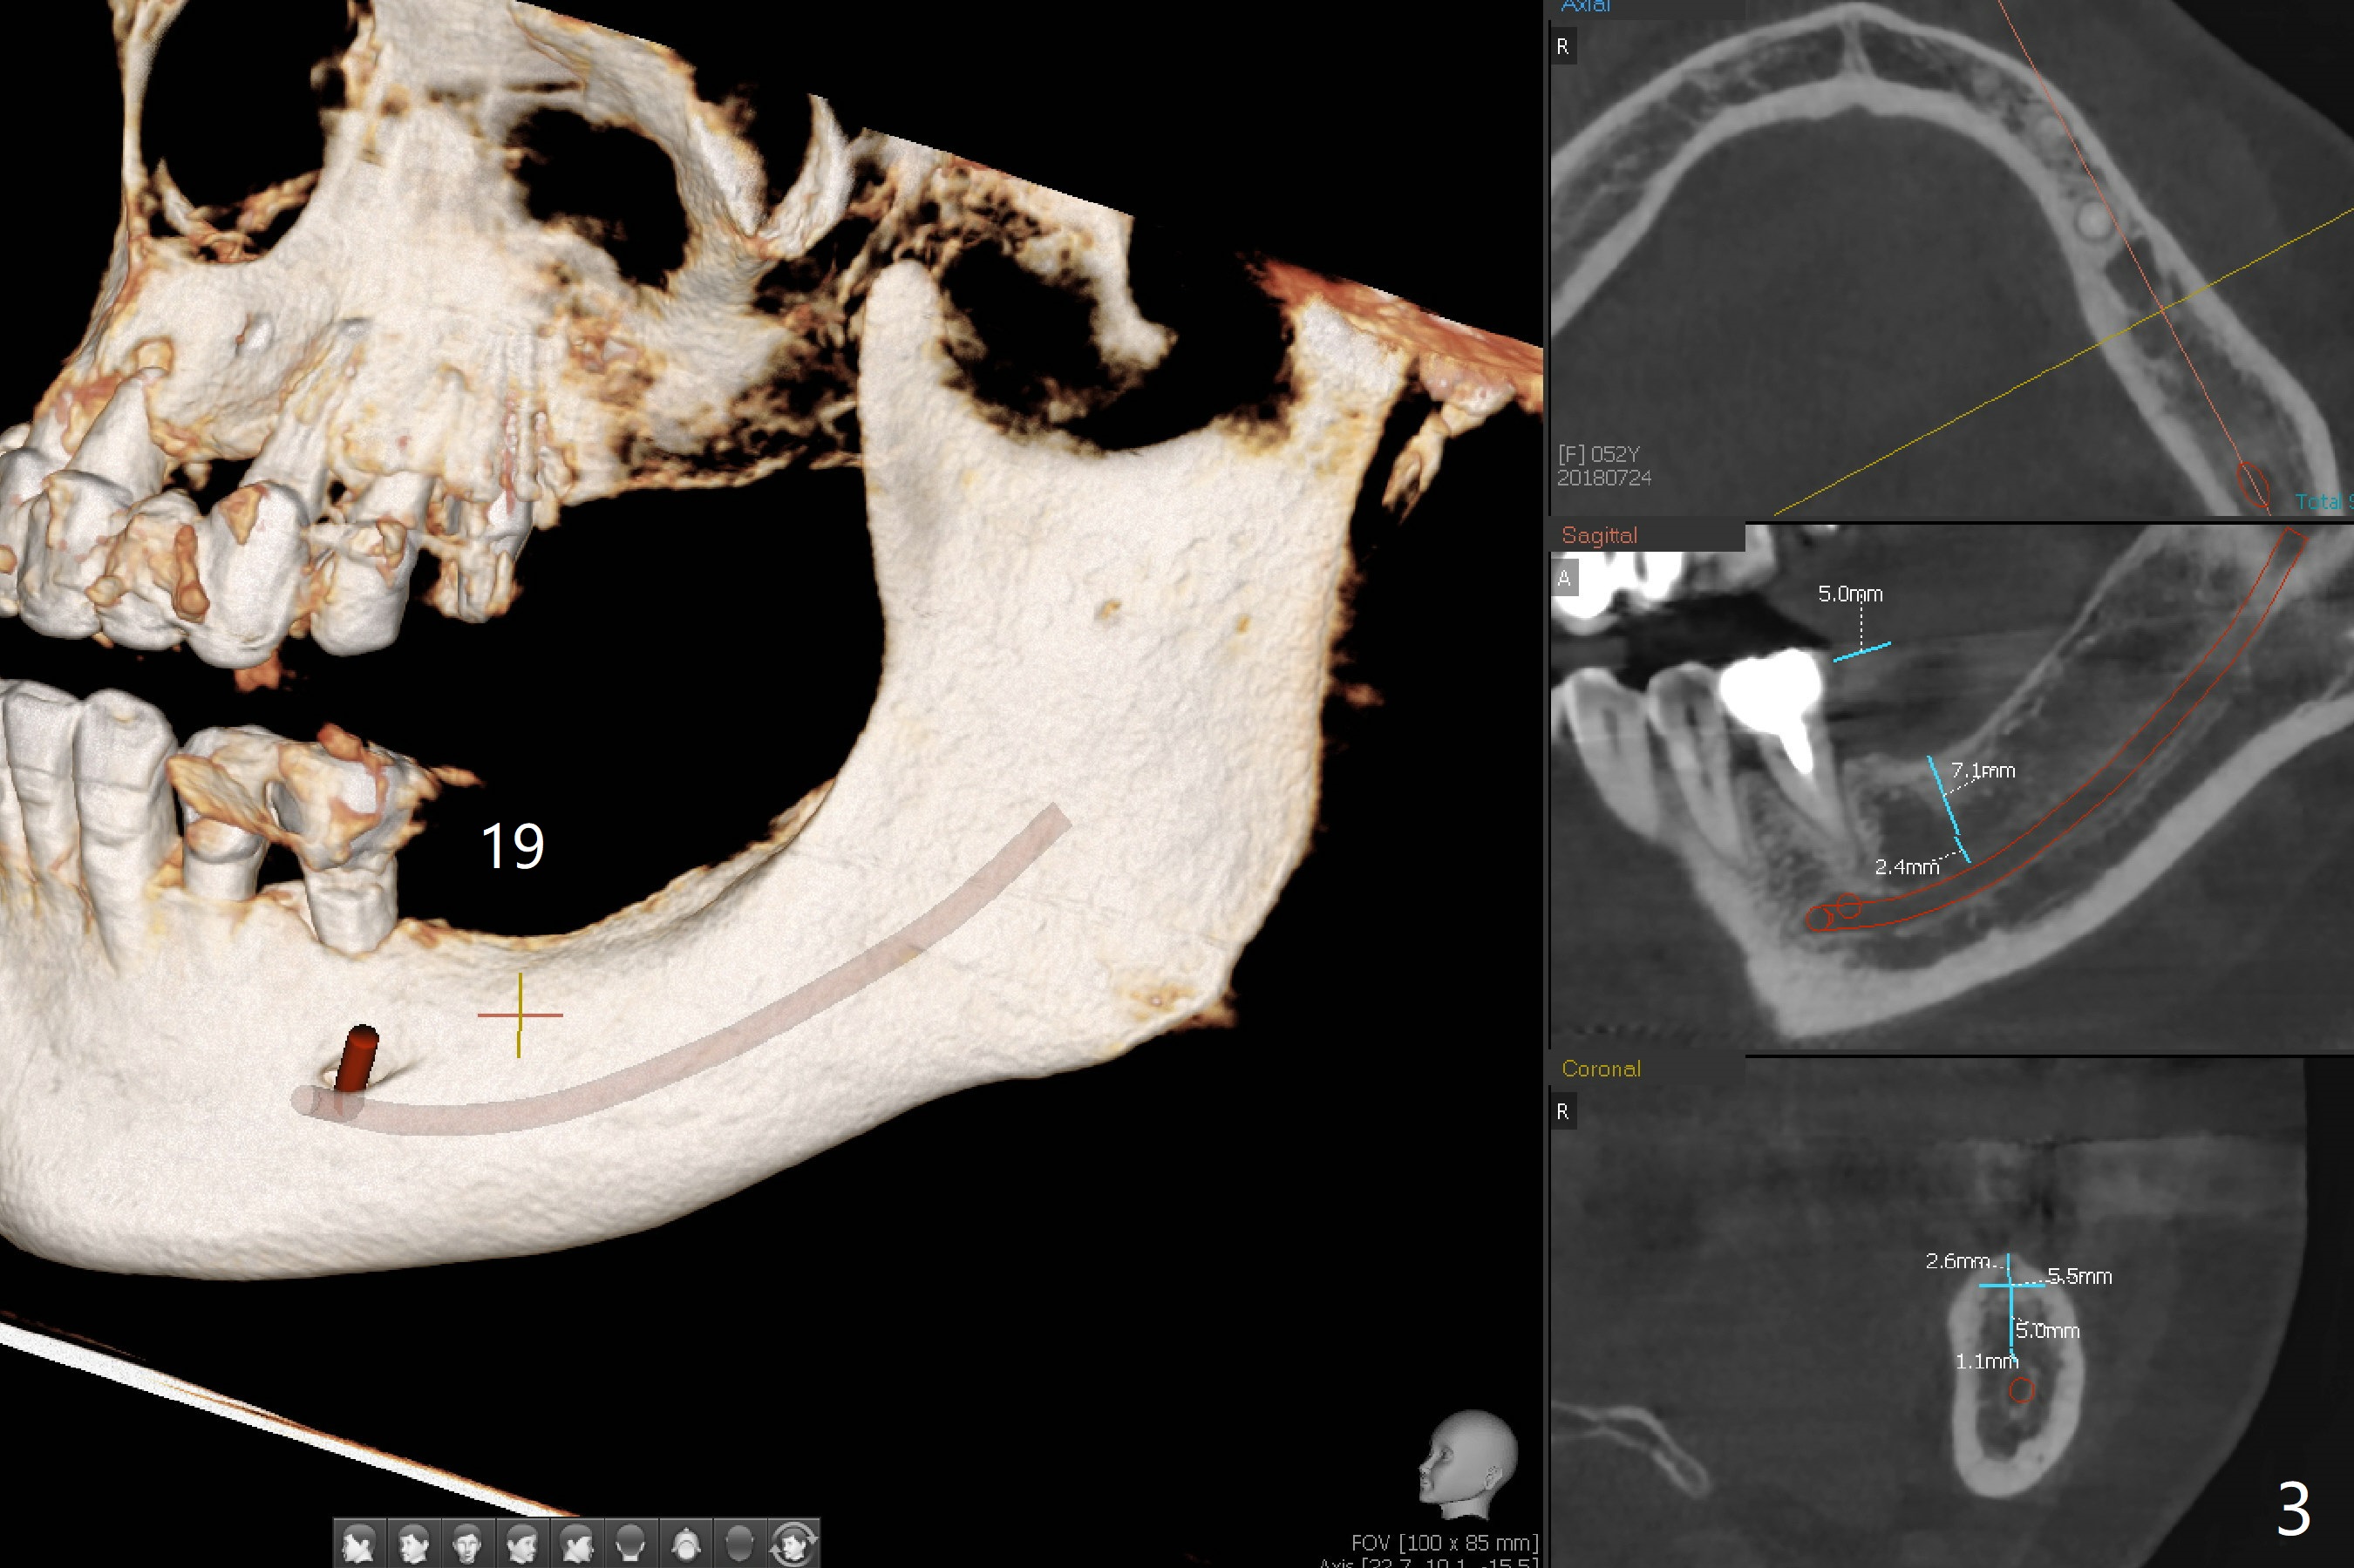

The bone height at #19 (Fig.3) allows placement of a 4x7.3 mm equicrestal or 5.5x5 mm subcrestal (Fig.4). A 4x8.5 mm UF implant (DIO, 1-staged ridge split) at #30 has been functionally 2 years 2 months post cementation. Since PVS impression for guide does not catch anatomy twice, Alginate impression will be taken for wax up and surgical stent. Use surgical handpiece and DIO Bone Expanders for 4x7.3 mm implant.